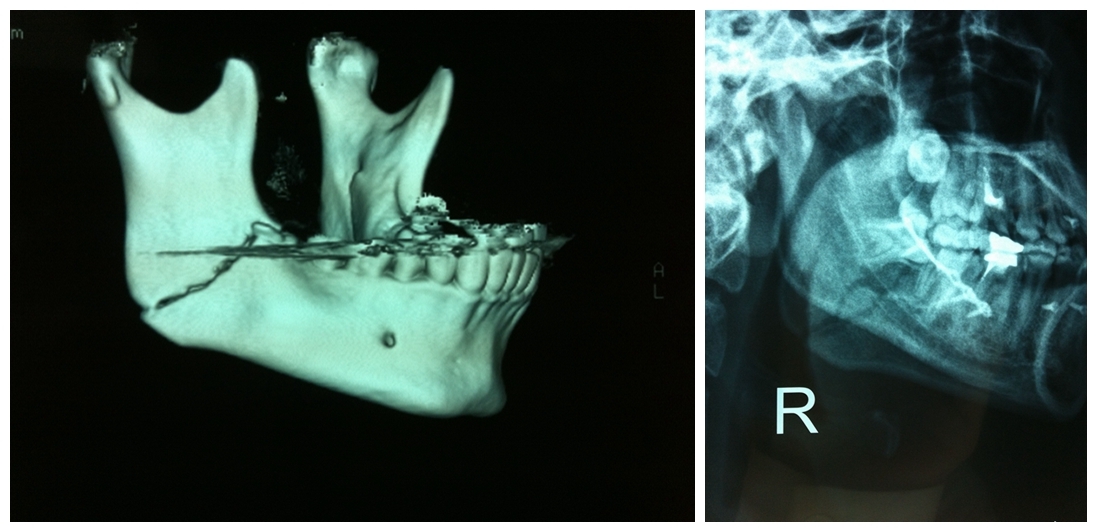

颌面部骨折导致的面容及咬合关系的改变

BO理论:不必过分强调解剖复位,更多着重咬合功能的恢复

坚强内固定联合变化的颌间牵引保证术中以及术后咬颌关系的恢复